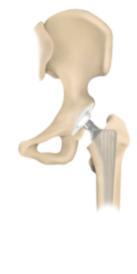

Bei den totalen Hüftendoprothesen (Hüft-TEP) werden in der Regel eine künstliche Hüftpfanne und eine Schaftprothese mit Aufsteckkopf implantiert. Hierfür stehen unterschiedliche Prothesenmodelle und Verankerungsmöglichkeiten (zementiert, zementfrei) zur Verfügung. Eine neuere operative Versorgungsmöglichkeit stellt der Hüftoberflächenersatz dar. Es handelt sich hierbei um ein besonders knochensparendes Prothesensystem, dessen klinischer Einsatz jedoch noch jung ist, sodaß potentielle Vorteile noch nicht abschließend beurteilt werden können.

Bei der zementierten Hüftprothese wird eine anatomisch angepasste Schaftprothese aus einer hochwertigen Edelstahllegierung (CoNi) über Knochenzement in der Markhöhle des Oberschenkelknochens verankert. Der Gelenkpartner zur künstlichen Hüftpfanne besteht in der Regel aus einem Keramikaufsteckkopf.

Als Pfannenersatz wird bei diesem Verfahren eine aus Polyethylen

bestehende Pfannenschale durch den Knochenzement im zuvor aufbereiteten

Pfannenlager befestigt. Vorteil der zementierten Hüftprothesen ist die

jahrelang zurückreichende Erfahrung mit diesen Systhemen, die sich zum

Teil über Jahrzehnte bewährt haben.

Bei der zementfreien Hüftprothese besteht die Schaftprothese aus einer speziellen Titanschmiedelegieung, welche das Anwachsen von Knochen fördert. Den Gelenkpartner zur künstlichen Hüftpfanne bildet ein Aufsteckkopf aus Keramik.

Als

Pfannenersatz wird in das zuvor aufbereitete Pfannenlager eine

subhemisphärische Titanschale eingepresst oder geschraubt, in welche

dann spezielle Polyethylen- oder Keramik-Inlays eingebracht werden.